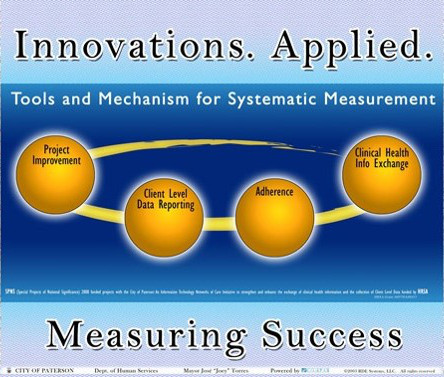

RDE Systems, maker of eCOMPAS®, has been serving public health for over twenty-five years. We are proud that RDE has grown only by referrals, and not through marketing and sales.

Our business philosophy is simple, yet refreshingly uncommon in the industry: "If you do good things for good people, good things happen."

We are leaders in over a dozen federal Special Projects of National Significance, which advance the state of the art in healthcare and resulted in significant positive impacts to health outcomes and published in international medical journals.